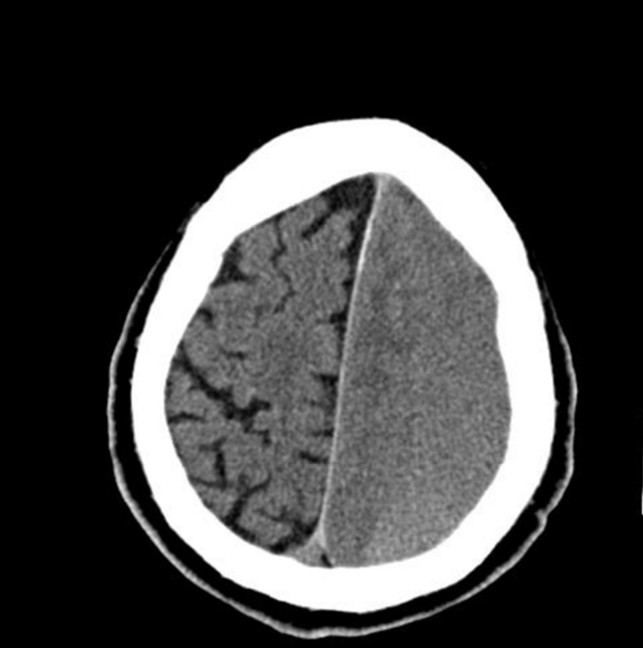

Acute confusion

A 79-year-old woman presents to your metropolitan ED with acute confusional state. She was last seen well by β¦